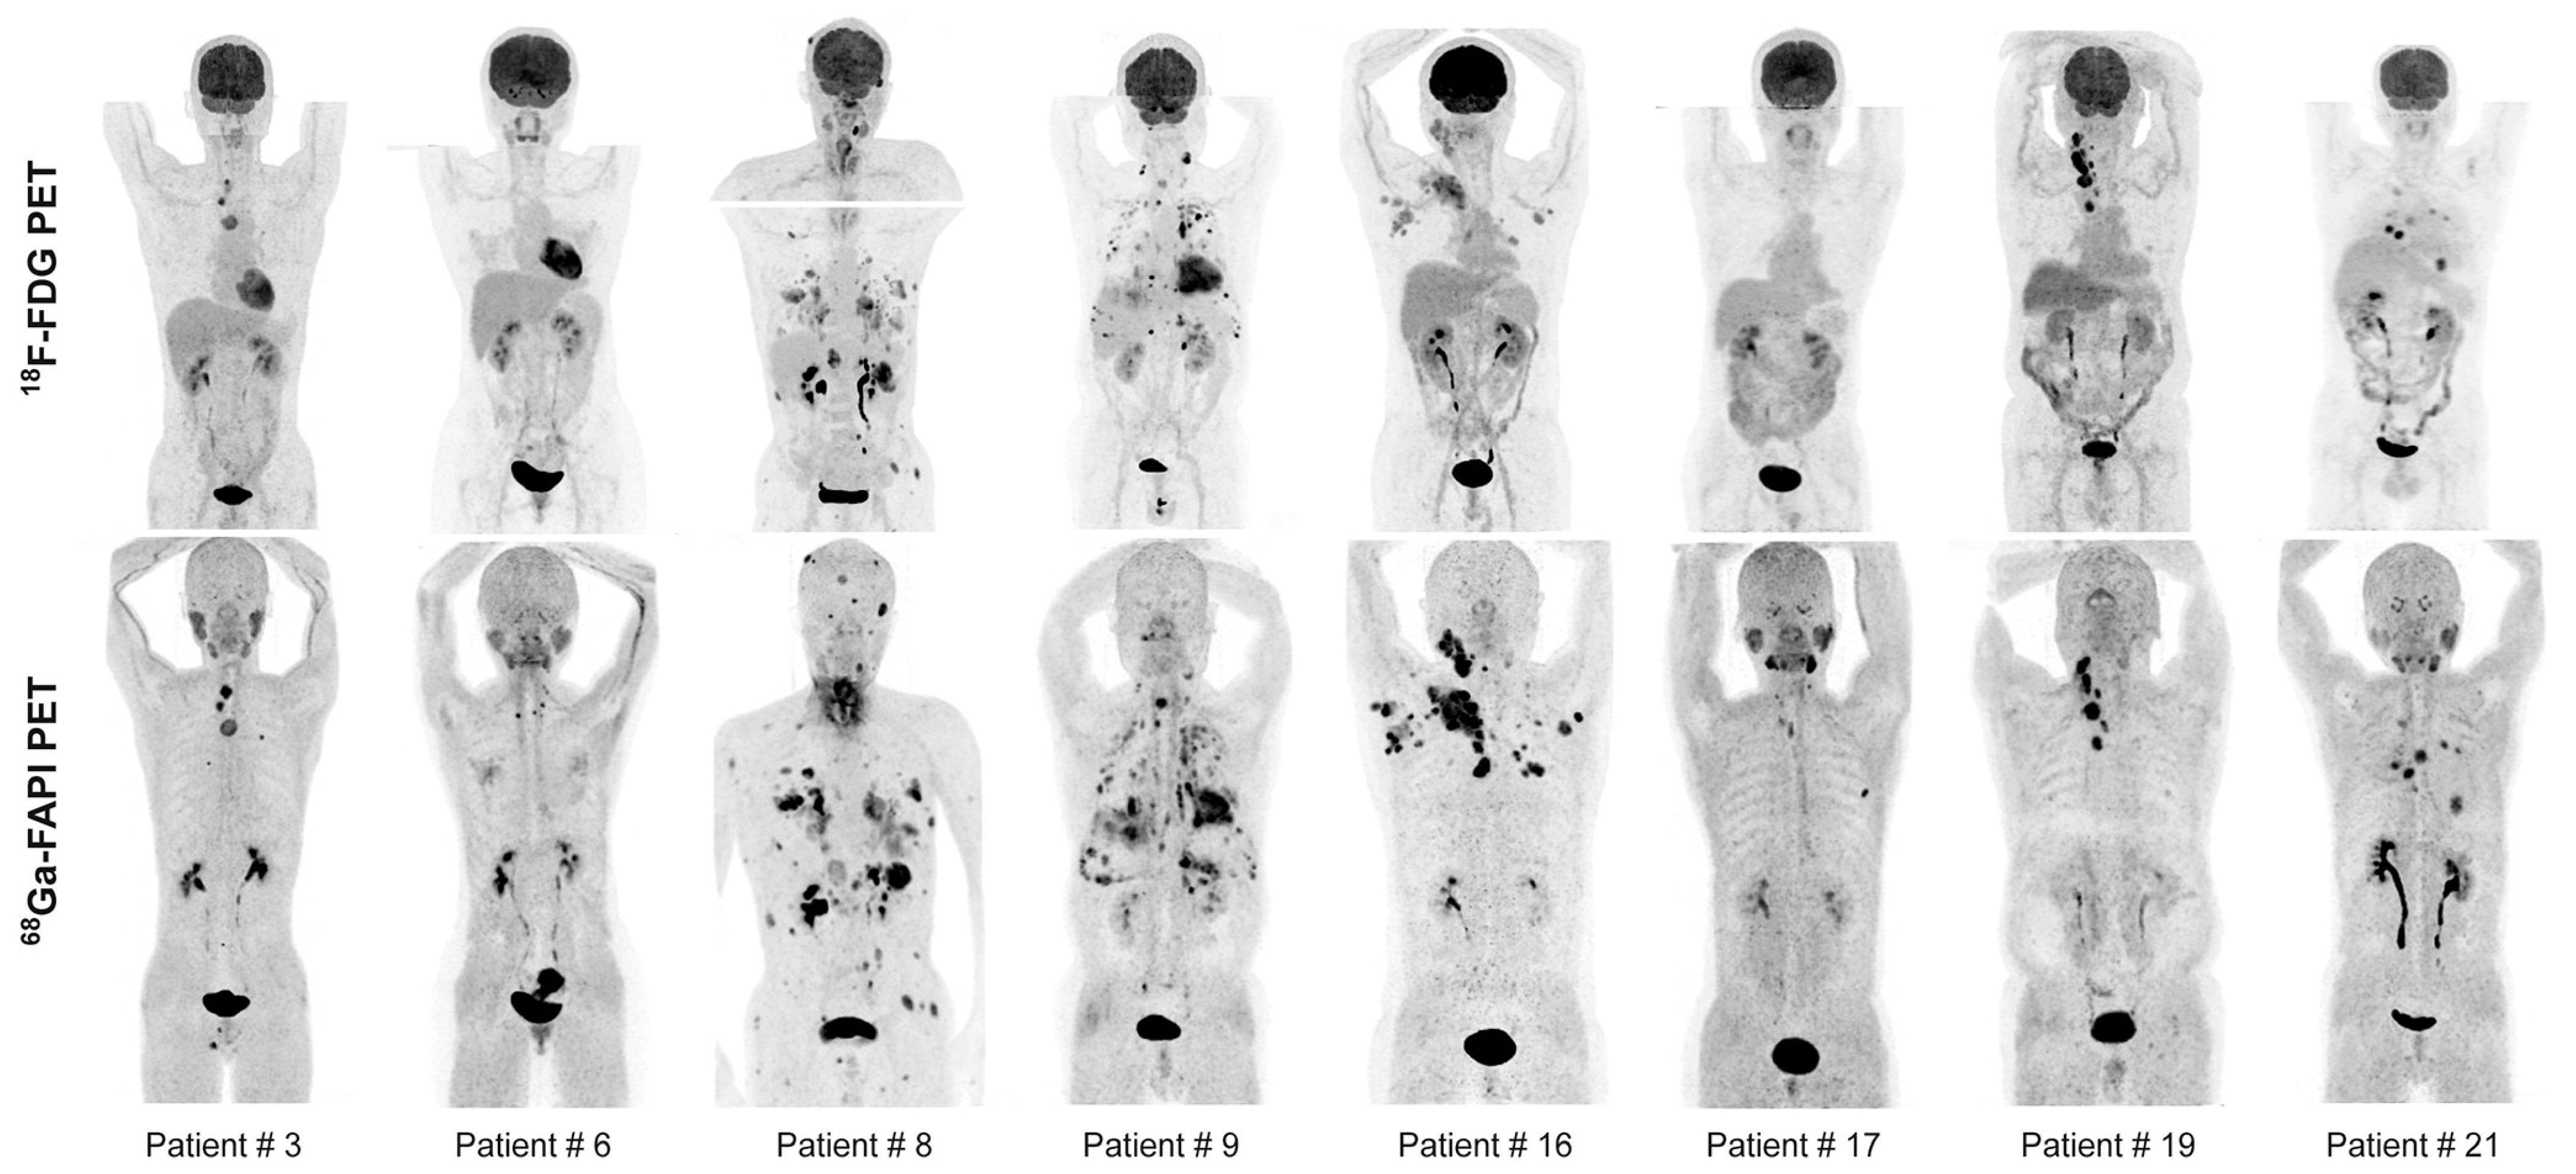

- Pang, Y.; Zhao, L.; Meng, T.; Xu, W.; Lin, Q.; Wu, H.; Zhang, J.; Chen, X.; Sun, L.; Chen, H. PET Imaging of Fibroblast Activation Protein in Various Types of Cancer Using 68Ga-FAP-2286: Comparison with 18F-FDG and 68Ga-FAPI-46 in a Single-Center, Prospective Study. J. Nucl. Med. Off. Publ. Soc. Nucl. Med. 2023, 64, 386–394. [Google Scholar] [CrossRef]